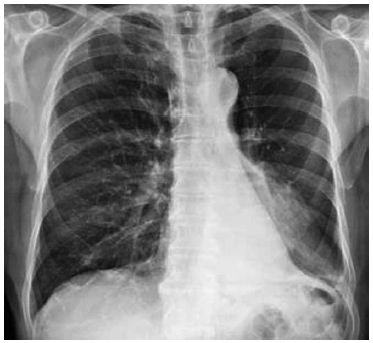

Qual é a principal anormalidade vista na radiografia a seguir?